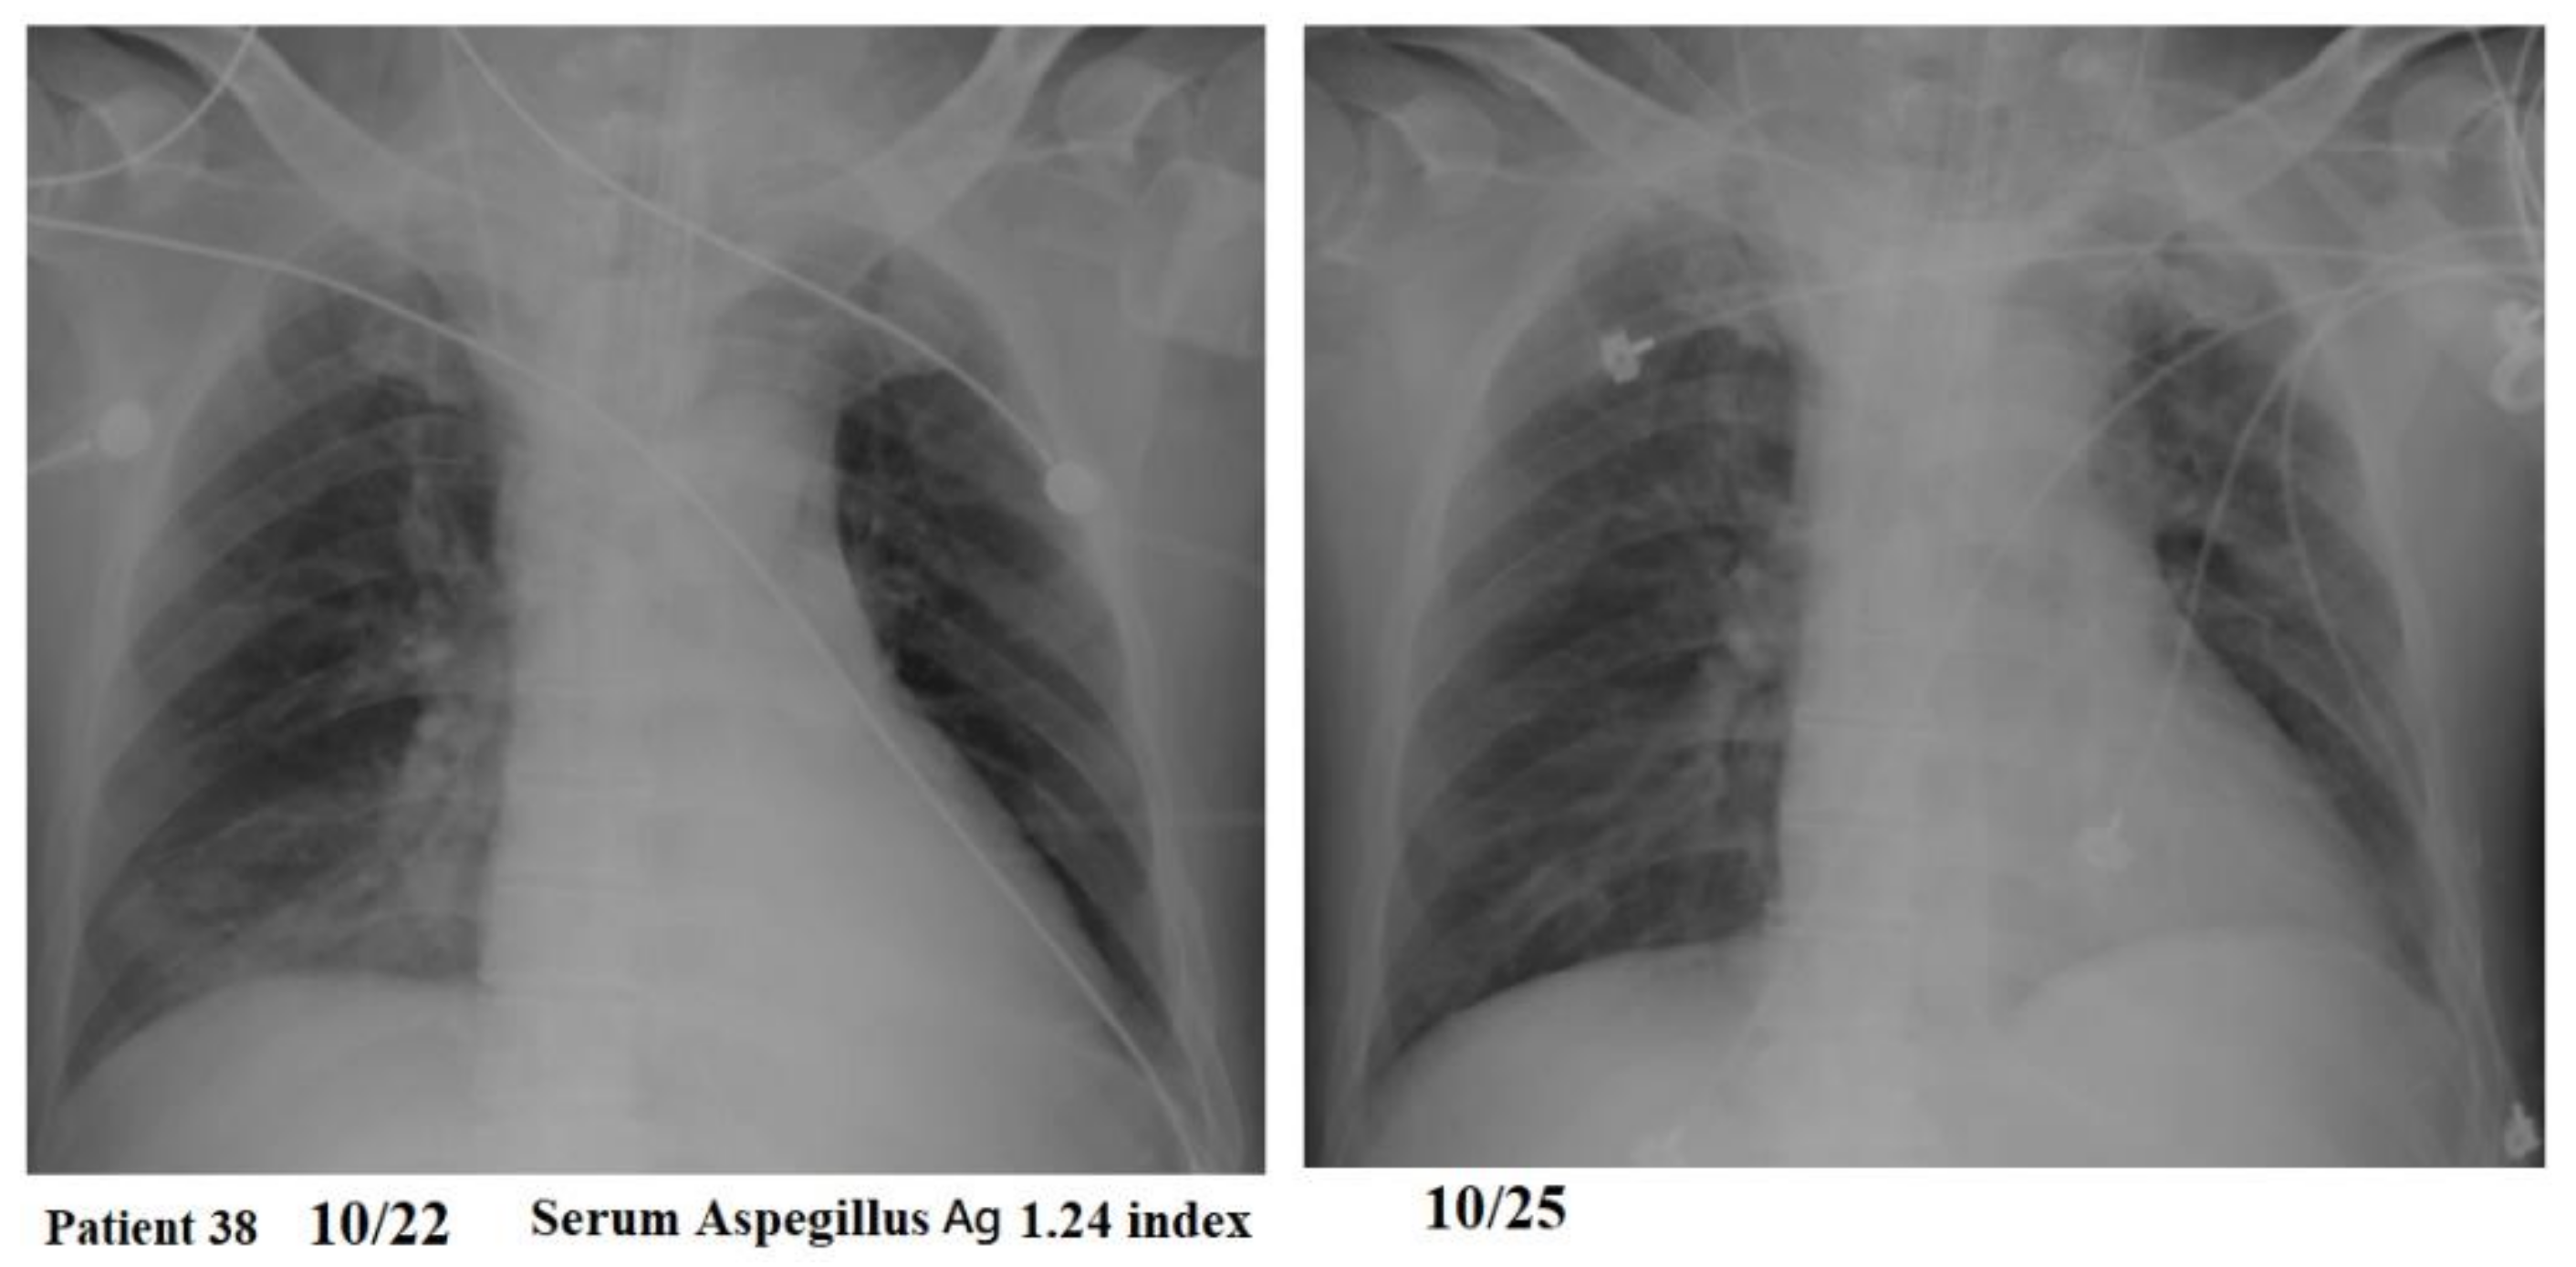

| Patient 38 | 48 M | yes | nil | 694 | 1 | 0 | survived | 9 | 1.24 | 0.19 |